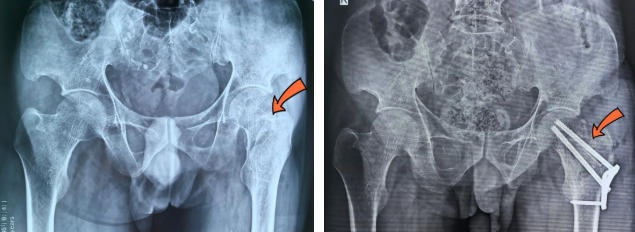

术前/术后

对此,医务科积极组织骨科、肾内科、手麻科等开展多学科会诊,充分评估病情,排除手术禁忌症后,最终确定实施股骨颈骨折切开复位内固定+带血管蒂腓骨移植术。前者可实现骨折断端精准对位固定,后者通过移植带血供的腓骨,为骨折区域提供充足血运。因患者是股骨颈头下型骨折,股骨头坏死率高,进行腓骨移植能给股骨头重建血供,减少坏死率,减轻患者痛苦。

骨科主任姬传磊向患者及家属充分说明手术方案并取得同意后,在手麻科配合下行手术,包括骨折固定和带血管蒂游离腓骨移植,需在显微镜下吻合血管,而血管直径仅为2mm至3mm,需要细心缝合,操作难度极大,对医生技术水平要求极高。

在团队的密切协作下,手术历时4个小时顺利完成,患者安返病房,目前正在进一步康复中。